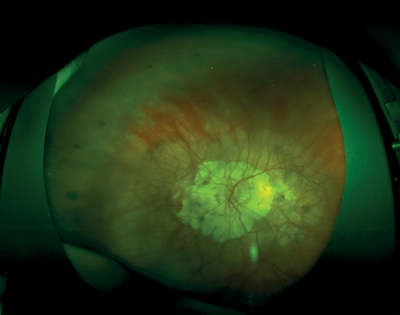

Fundus examination demonstrated bilateral myopic macular degeneration. There was extensive peri-papillary atrophy and thin optic nerve neuro-retinal rims in both eyes (Figure 4).

Figure 4: Wide-field fundus image of the left eye. Typical myopic fundus with extensive peripapillary atrophy.